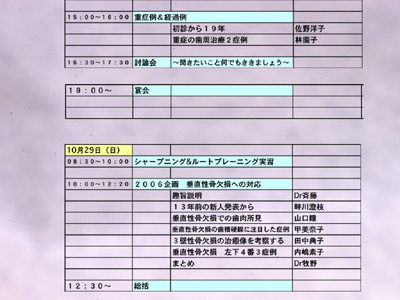

スタッフミーティングに臨む前に参加者にひとつの症例を提示し、その予後を予測してもらいました。

症例:’93初診時、右下45遠心に垂直性骨欠損がありプロービングデプス>8〜9mmでした。(当時の)新人DH Kによる非外科的ルートプレーニングにてPD2〜3mmに減少し、歯槽骨頂線が明瞭になりました。当時はそれを骨吸収の停止すなわち安定と考え一応のゴールの目安としていました。でも「その後」はみてはいませんでした。

「それから13年後の2006年、この骨はどのように変化したでしょう?」というのが宿題です。

それを頭のすみに残しながら各医院が垂直性骨欠損への対応としての症例を提示しました。また骨欠損とレントゲンの注意事項を川上先生斉藤先生が模型実験で示してくれました。

さて宿題の症例にもどって、13年後の解答です。

レントゲン上でもリエントリーでの肉眼所見でも骨欠損は認められませんし、ふたつの実験結果からの反証とも異なると思います。

今回の症例では咬合調整は一切行っていません。ルートプレーニングのみによる大きな治癒の可能性を再確認しました。プロービングデプス、デンタル上での骨欠損とその変化、歯周病の治癒の様式etc.いくつものテーマが示唆されると思います。いずれも「剱Basic」として繰り返し学んでいることです。

垂直性骨欠損には咬合性外傷を伴うものがおおいため、咬合調整をして自然移動をはかり骨レベルを揃えるという手法がとられる事が多いですが、非可逆的処置である削合とくに抜髄を伴うときなどは、そのリスクベネフィットバランスをよく天秤にかける必要があることは当然です。